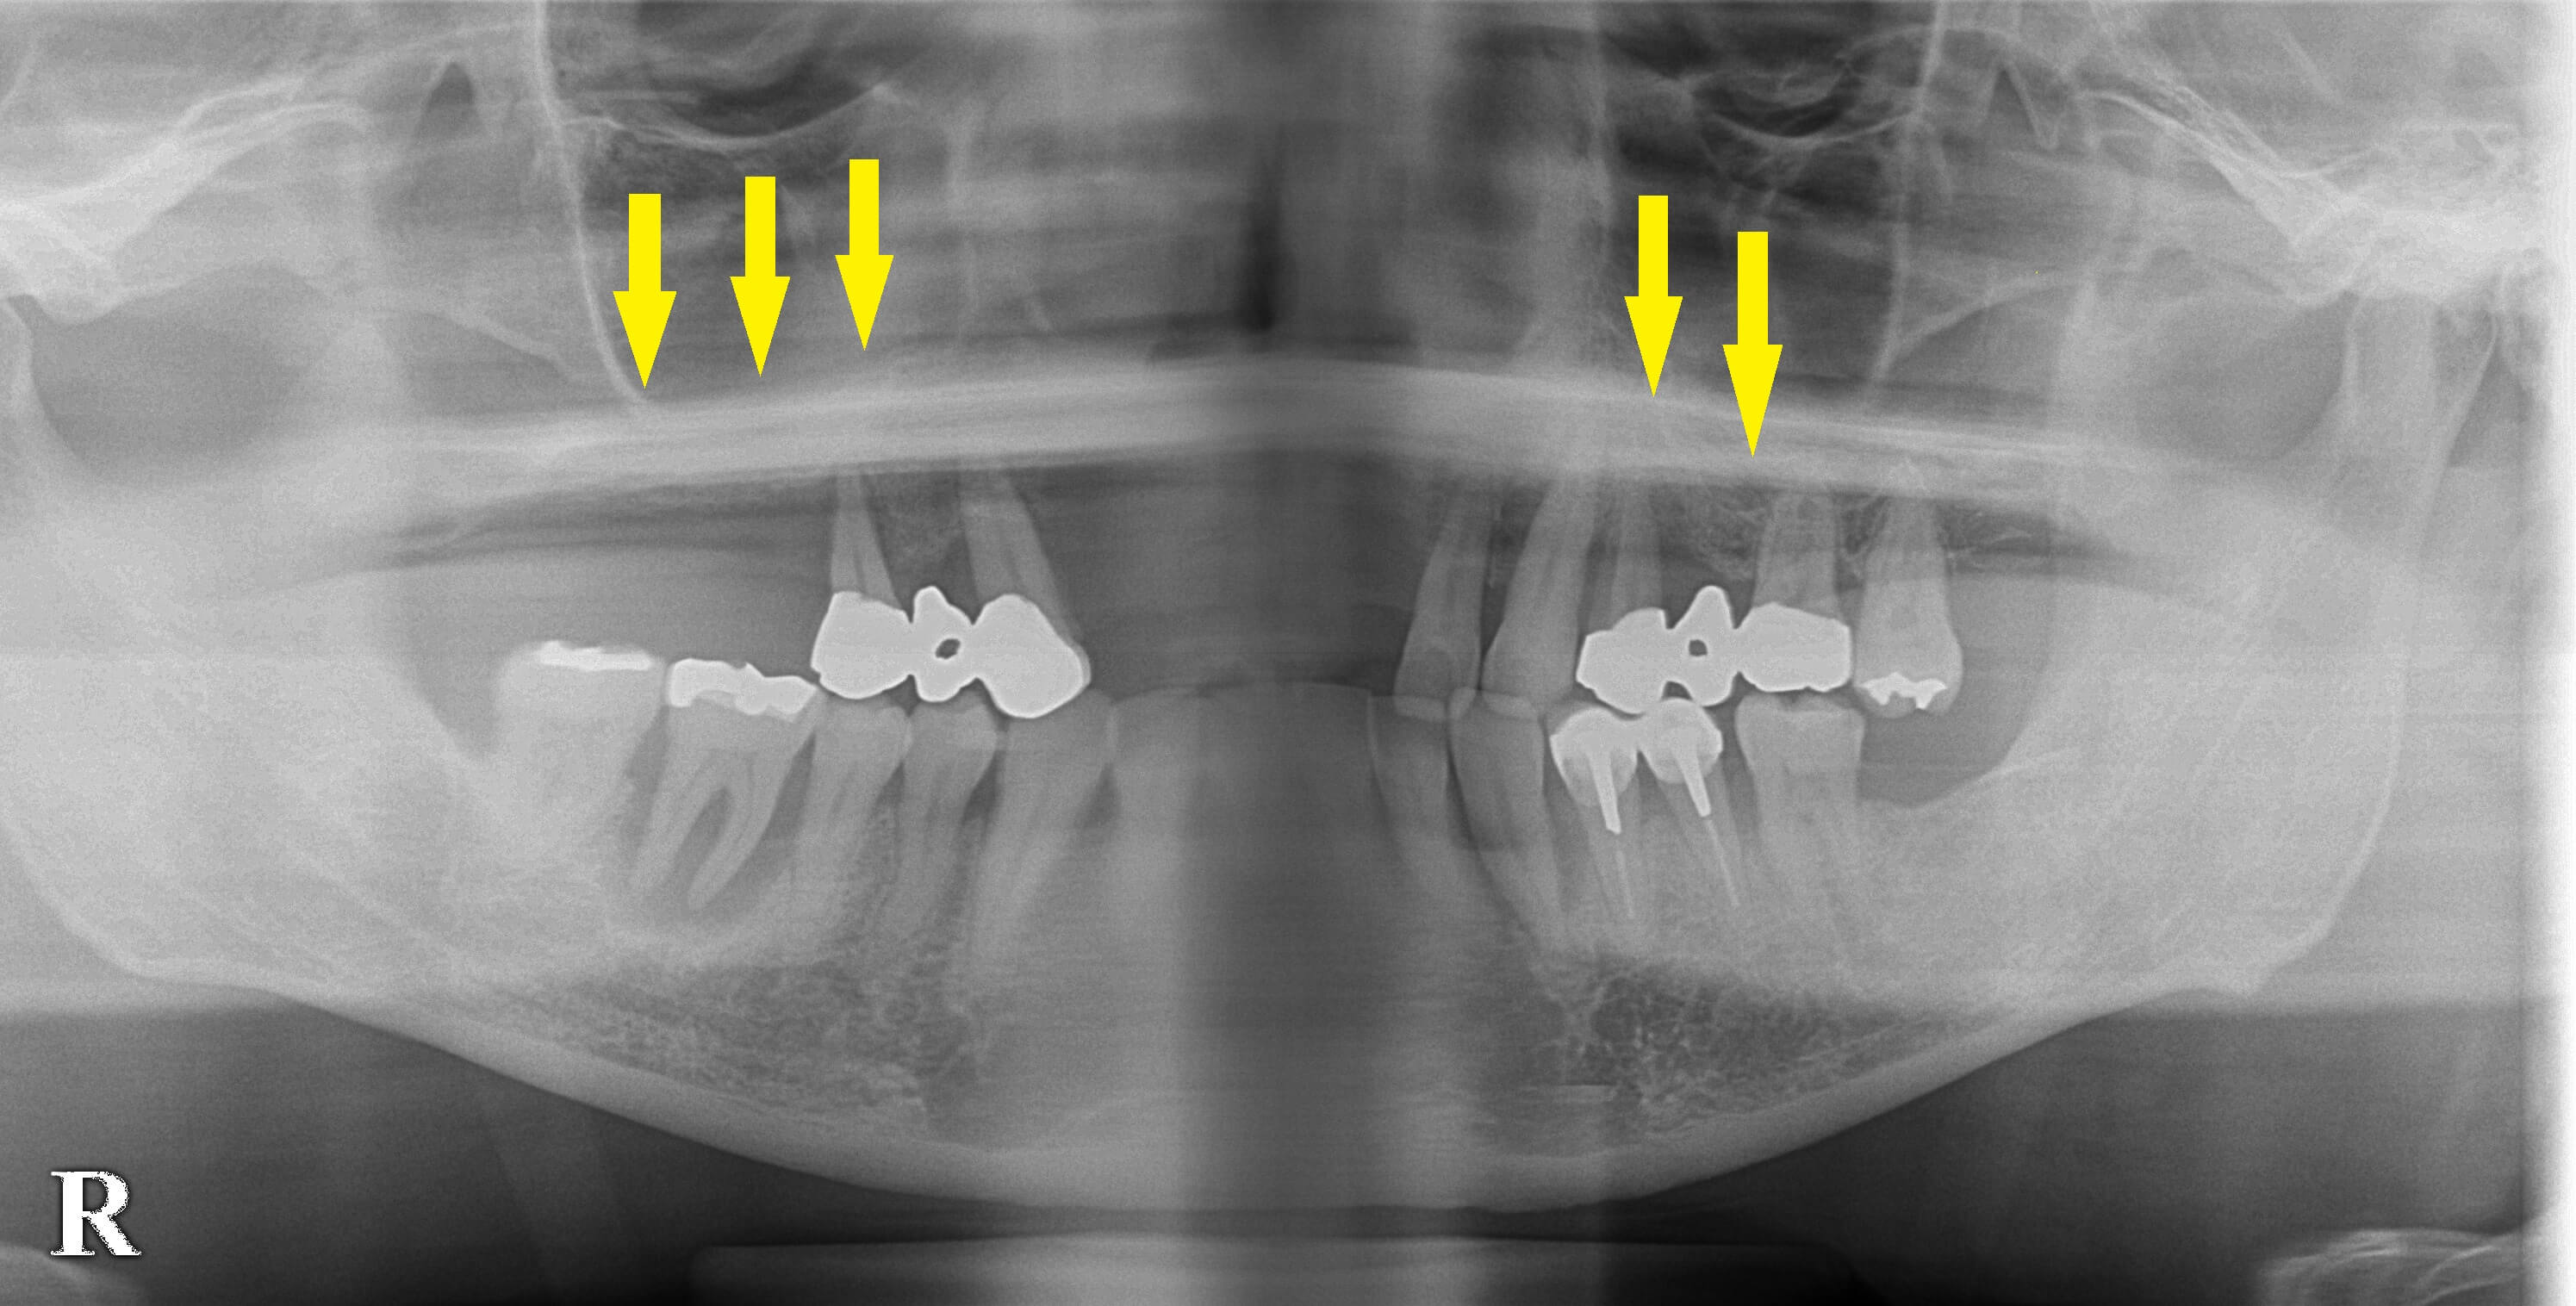

臼歯部は骨が薄いため、両側ともサイナスリフトという、骨造成を行ってインプラント埋入を行いました。

下の写真2段目が手術前のCT、3段目の写真が、骨造成が終了し、インプラント埋入後のCTです。

薄かった骨が造成され、インプラントがしっかりと埋入できています。